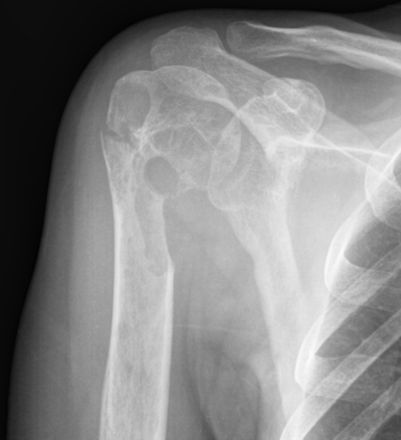

Какая патология по Вашему мнению, коллеги, на снимках?

1. В обоих случаях - мета-эпифиз (а там, даже у взрослых - крастный костный мозг).

2. Полостные структуры.

3. В первом и во втором случаях - дефекты кортикального слоя с остеопоротической компонентой. На левом снимке и полее мелкие полостные образования.

Я на 1 место поставлю любимый мною "тубер", на второе - "мета"

Еще версии? обратите внимание на скиалогию очагов! Ничего не напоминает?

Ну, не ГКО-же?

На мой взгляд, здесь озлакочествленное что-то первично доброкачественное (во загнул).

А почему нет?